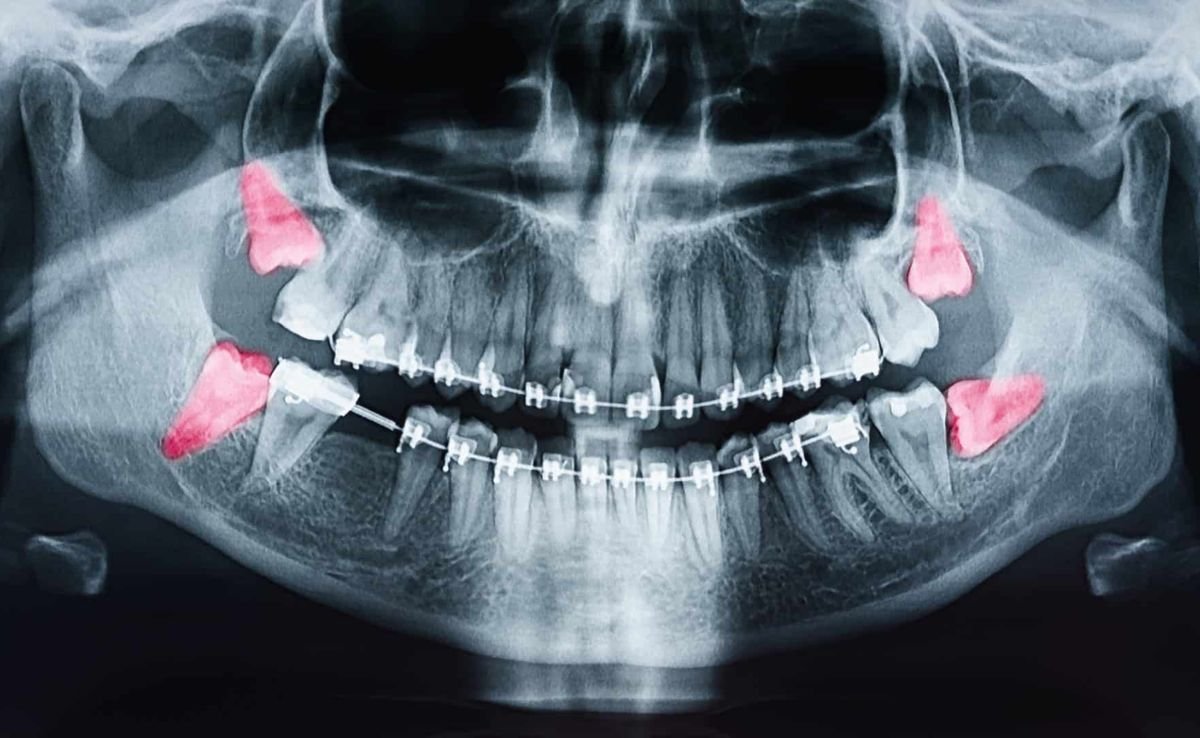

Wisdom teeth, or third molars, often emerge misaligned or impacted, causing pain or infection. Surgical extraction may be necessary to prevent crowding.

The process starts with undergoing digital imaging such as X-rays or CBCT scans, which help evaluate the condition of your teeth, jawbone, and soft tissues. The surgeon then creates a personalised treatment plan, explains the procedure, and addresses any concerns or risks.